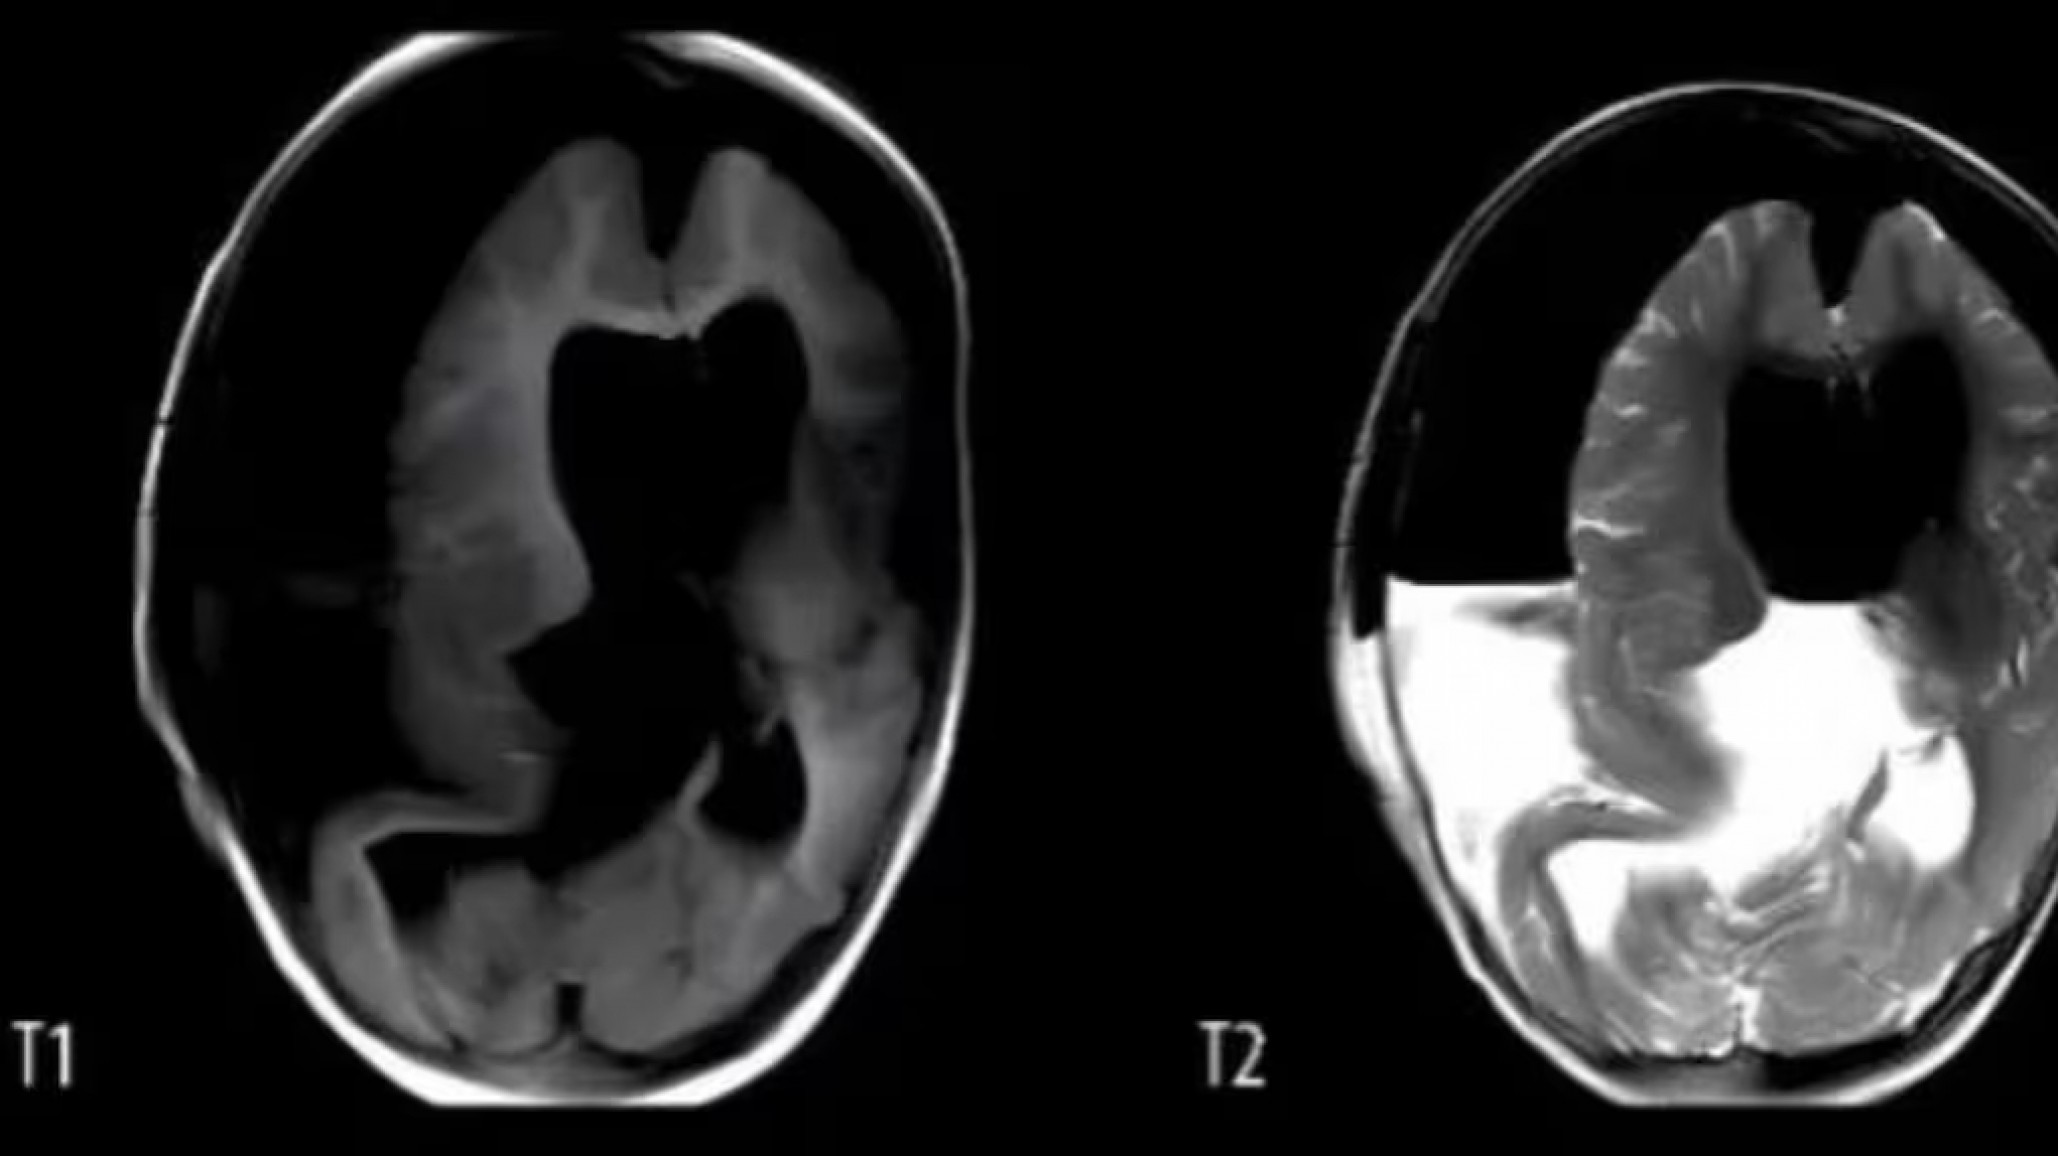

La pequeña había sido hospitalizada debido al tamaño anormal de su cráneo y retrasos en sus habilidades motoras. Una tomografía reveló la presencia de tejido óseo similar al de las extremidades y sombras de tejido mixto en el área intracraneal, lo que llevó a los médicos a realizar una craneotomía.

Los médicos habían detectado anomalías en el cráneo de la niña a las 33 semanas de gestación, durante un examen prenatal, aunque una resonancia magnética no proporcionó más información. La niña nació por cesárea a las 37 semanas con un cráneo notablemente grande. Al año de vida, su cráneo era anormalmente grande y solo podía decir "mamá" y mover ligeramente la cabeza, sin poder sentarse ni gatear.